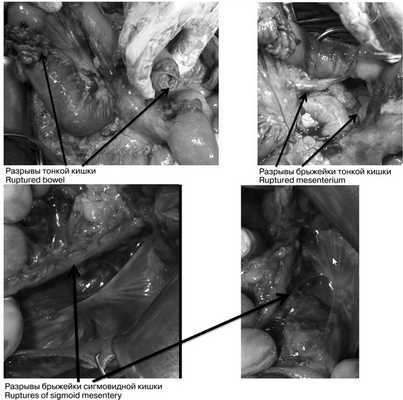

При динамическом наблюдении отмечено нарастание явлений геморрагического шока. С учетом клинико-инструментальной картины заболевания закрытой травмы живота с повреждением внутренних органов и продолжающимся внутрибрюшным кровотечением в экстренном порядке выполнена лапаротомия. Во время доступа в брюшную полость выявлено, что кожа и подкожная клетчатка полностью отсепарированы от подлежащего слоя прямых и косых мышц, имбибированных кровью из-за размозжения (межмышечная гематома) на всем протяжении доступа. Множественные более мелкие гематомы в подкожной клетчатке. В брюшной полости во всех отделах большое количество крови и сгустков (1800 мл), кровь аспирирована с помощью аппарата CellSaver. Продолжающегося активного кровотечения не выявлено. При ревизии органов брюшной полости: в проекции V—VI сегментов правой доли печени по краю выявлена подкапсульная гематома размером около 6×2 см, не пульсирующая, в объеме за время операции не увеличилась. Других повреждений печени по диафрагмальной и висцеральной поверхностям не установлено; на расстоянии 30, 40 и 45 см от связки Трейца 3 разрыва стенки тощей кишки с вскрытием просвета и 1 десерозированный участок. В области разрывов кишки также отмечены участки повреждения брыжейки тонкой кишки (рис. 3), Рис. 3. Разрывы петель тонкой и толстой кишки (интраоперационные фотографии). откуда продолжалось кровотечение. На расстоянии 60 см от связки Трейца выявлен полный поперечный разрыв тощей кишки с разрывом брыжейки кишки до уровня ее корня и активно продолжающимся кровотечением из сосудов брыжейки. Гематома в области брыжейки поперечной ободочной кишки, просвет кишки не вскрыт, гематома в размерах не увеличивается. Помимо этого гематома околокишечной клетчатки вдоль нисходящей ободочной кишки и сигмовидной кишки, брыжейка которой на уровне дистальной трети разорвана; сама сигмовидная кишка в области разрыва брыжейки не изменена, спастически сокращена, просвет не вскрыт, серозная оболочка обычной окраски с небольшими петехиальными кровоизлияниями из-за травмы. Обширная забрюшинная гематома по левому латеральному каналу с распространением на парааортальное клетчаточное пространство и корень брыжейки тонкой кишки. Париетальная брюшина в области левого латерального канала также разорвана, визуализирован левый мочеточник, без повреждений (моча концентрированная, макрогематурии нет). В области боковой стенки живота со стороны париетальной брюшины разрыв стенки размером около 10×5 см с повреждением прямых и косых мышц живота и продолжающимся низкоинтенсивным кровотечением из мышечных сосудов.

Выполнена резекция 30 см тощей кишки, начиная с первого разрыва на 30 см от связки Трейца до полного поперечного разрыва на 60 см с формированием энтероэнтероанастомоза конец в конец. Произведена назоинтестинальная интубация. Далее ушиты поврежденные мышцы передней брюшной стенки и восстановлена непрерывность париетальной брюшины. Брюшная полость промыта 3000 мл 0,9% раствора NaCl, установлены двухпросветные дренажи в полость малого таза, в правое подпеченочное пространство и в левый латеральный канал. Выполнена петлевая трансверзостомия.

В экстренном порядке выполнена диагностическая лапароскопия: в брюшной полости мутный геморрагический выпот до 300 мл во всех отделах живота, на висцеральной брюшине мезогастральной области налет фибрина. На расстоянии 80 см от илеоцекального угла сквозной дефект тонкой кишки с вывернутыми краями размером 3×2 см. Принято решение о конверсии — выполнена широкая срединная лапаротомия. В брюшной полости 450 мл геморрагического содержимого с примесью кишечного отделяемого. В 80 см от илеоцекального угла определяются 3 линейных разрыва подвздошной кишки диаметром до 1,5 см (рис. 5). Рис. 5. Множественные разрывы стенки тонкой кишки (интраоперационные фотографии). Брыжейка тонкой кишки с множественными поверхностными разрывами, кровоподтеками, гематомой (рис. 6). Рис. 6. Разрыв брыжейки тонкой кишки (интраоперационная фотография). В верхней трети сигмовидной кишки дефект серозно-мышечного слоя размером 2×1 см. При дальнейшей ревизии повреждений желчного пузыря, желудка, начального отдела двенадцатиперстной кишки не выявлено. Выполнена резекция около 15 см участка подвздошной кишки с тремя разрывами. Сформирован энтероэнтероанастомоз конец в конец. Произведена назоинтестинальная интубация. Выполнено ушивание дефекта стенки сигмовидной кишки. Произведено дренирование брюшной полости в полость малого таза, правое подпеченочное пространство и в левый латеральный канал.